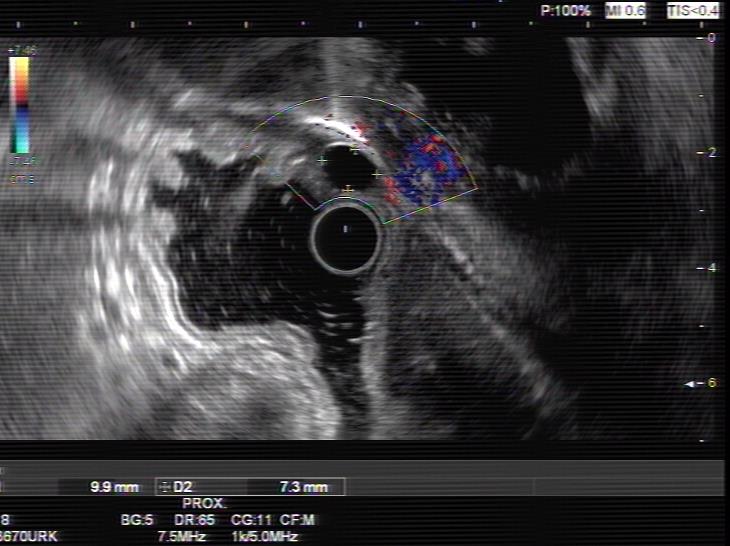

患者,66岁,女性,平素身体健康,以“发现胃肿物2年余”主诉入院,既往于外院行电子胃镜检查发现胃底隆起,直径约1.5-2.0cm,超声内镜检查考虑黏膜下来源间质瘤可能,不除外壁外病变压迫。外院CT提示胃底浆膜下囊性病变可能。患者及家属诊治心切,辗转数家医院后为求内镜下治疗遂来二附院。入院后在消化内科再次超声内镜检查,提示胃壁增生病变可能,增强CT提示胃底胃壁增厚,结合内镜检查。患者及家属强烈要求内镜下探查及病变切除术。术前在王进海主任的指导组织下,进行了专业组内及多学科讨论,与患者及家属充分沟通后,决定行内镜下切开探查及病变治疗术,必要时可行内镜-腹腔镜联合手术(LECS)。邹百仓教授带领内镜下肿瘤诊治及超级微创手术团队施行手术,术中逐层切开胃壁黏膜层及黏膜下层,暴露固有肌层,未发现胃壁病变,遂切开胃壁全层,局部腹腔探查,切口附近腹腔内似韧带组织上发现半球形隆起,表面透亮光滑,大小约1.5X1.5cm,术中请外科李军辉及袁庆攻教授会诊后确诊为囊性病变,讨论后建议可以观察或内镜切开引流,与患者家属沟通后家属强烈要求切开引流,遂用内镜切开刀切开囊肿,引流少量清亮囊液,囊肿塌瘪,观察囊肿切口及局部无出血,切除局部部分胃壁组织送检,内镜下严密关闭切口,留置胃管后,返回病房,常规对症治疗1周,患者无并发症发生,正常出院。

上腹部增强CT 超声内镜